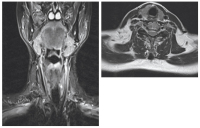

MR Malformation

Abbildung 5: MR mit Darstellung einer großen lymphatischen, makrozystischen Malformation zervikal rechts.

Keywords: GefäßmedizinlymphatischmakrozystischMalformationMR

Kontrolle 3 Monate nach Sklerosierung

Abbildung 6: Kontrolle 3 Monate nach Sklerosierung ohne Hinweis auf einen Rest- oder Rezidivbefund.

Keywords: GefäßmedizinMRRestbefundRezidivbefundSklerosierung